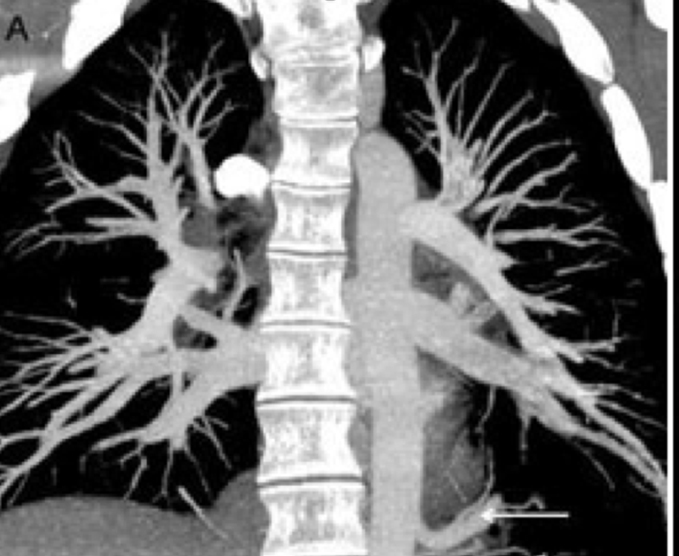

Angiotomografías

La angiografía por TC (ATC) combina una tomografía computarizada con la inyección de una tintura de contraste. TC significa tomografía computarizada. Esta técnica es capaz de crear imágenes de los vasos sanguíneos para detección de anomalías.

- Arterias pulmonales